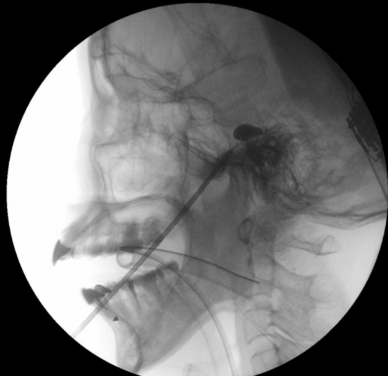

「經皮球囊壓迫術」屬微創介入技術,用於緩解與三叉神經相關的疼痛。而三叉神經負責面部感覺,當其功能異常時,會引發劇烈的面部疼痛。醫生會經面頰穿刺將微型球囊導管置入顱底的三叉神經節,用顯影劑擴張球囊,壓迫痛覺神經纖維。術中通過透視影像確認球囊呈梨形外觀以確保位置準確,從而精準阻斷痛覺傳導。